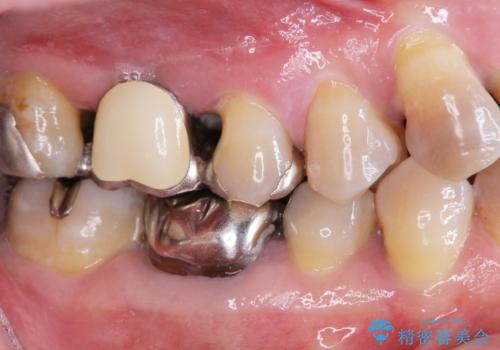

検査の結果、重度の歯周病であることから保存が難しい歯は抜歯を行いインプラントを、残すことが可能な歯には再生治療を含めた歯周病治療を行いより多くの歯を残す歯周病治療を計画します。

また咬合負担に不安のある前歯を助けるためにも、臼歯部にインプラント補綴を行いしっかりとかめる状態とすることも大切です。